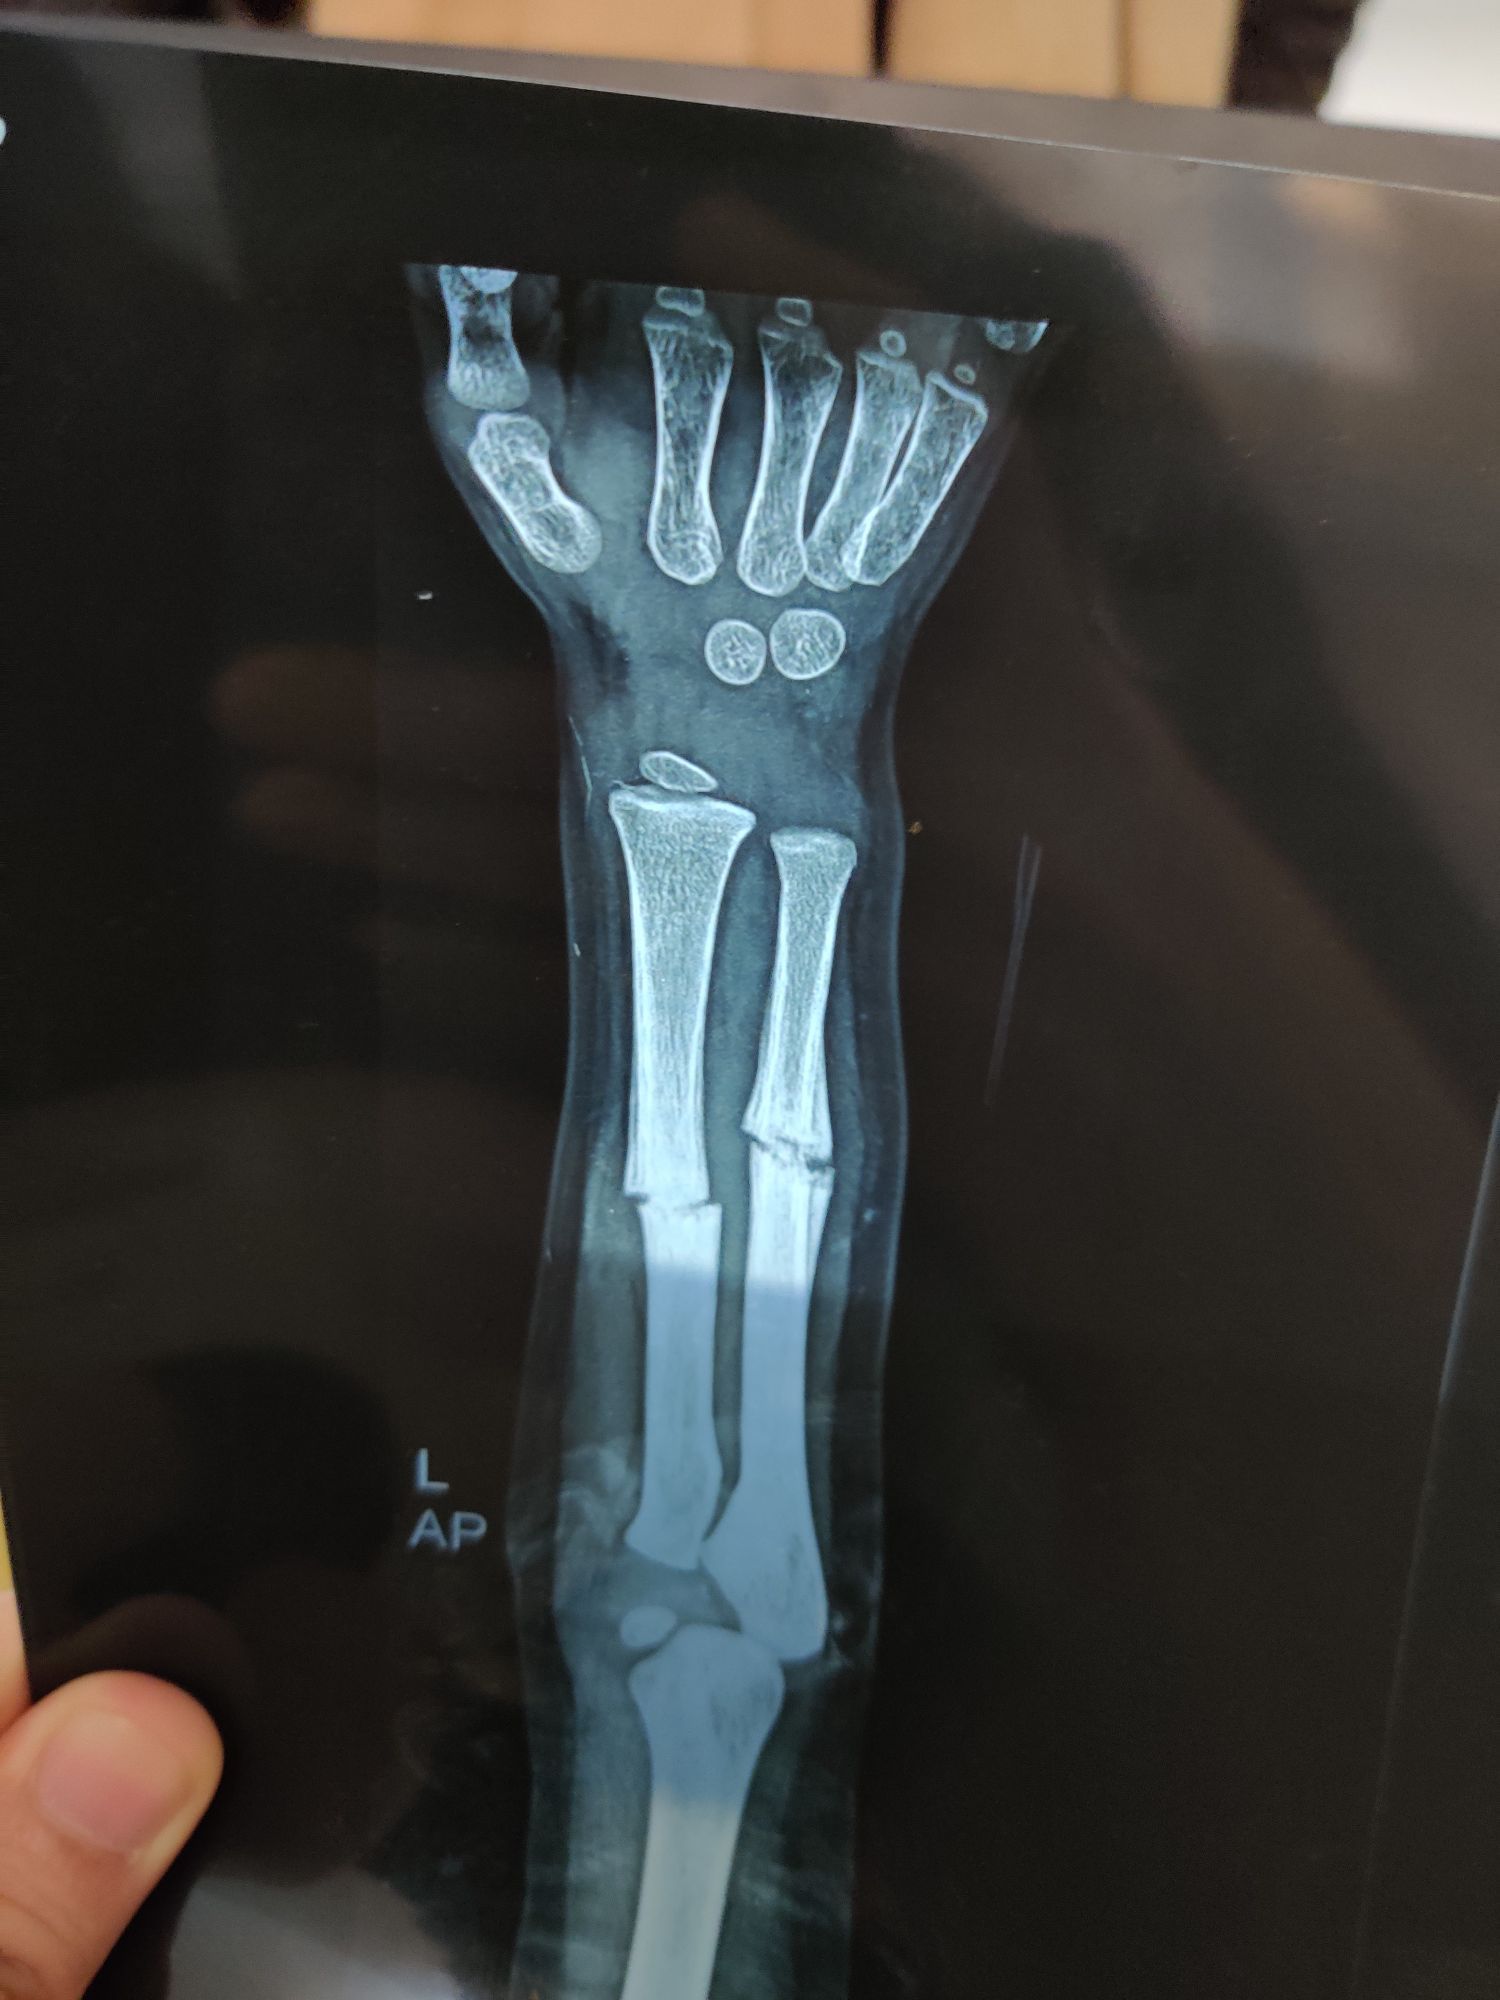

Fracture Radius + Ulna

Radius

Ulna